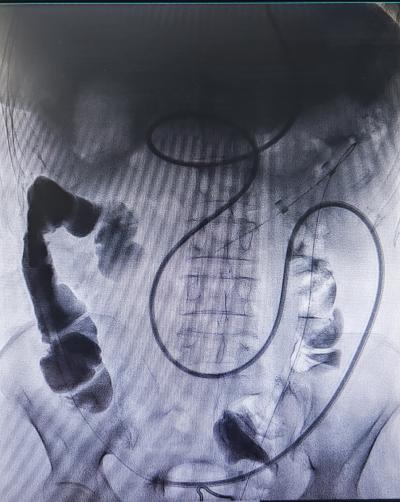

介入置管后造影

肠梗阻导管

入院后完善相关检查,经介入团队留置肠梗阻导管(经鼻型、经肛型),肠梗阻导管由硅橡胶制成,富于柔韧性,有效吸引肠道内容物,充分减轻肠道压力、肠道准备,为患者能够行全腹腔镜全结肠切除提供了重要的先决条件。我院普外三科邵学谦主任及其团队在手术室团队的协助下完成了全腹腔镜下全结肠切除术。术后患者病情恢复良好,便秘症状得到了完全缓解,生活质量得到了显著提高。